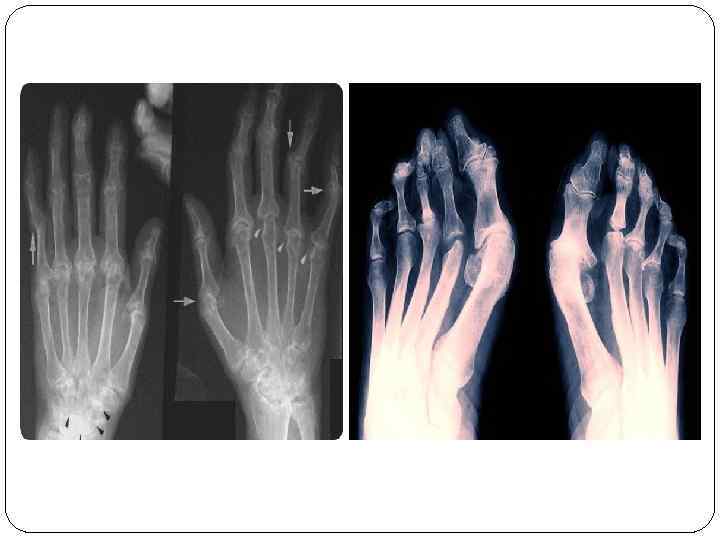

Клиника РА 3 сатылық клиникамен сипатталады: I саты: - синовиальды қабатта периартикуларлы ісіну болады; II саты: - синовиальды қабаттың жұқаруына әкелетін, жасушаның ыдырауы; III саты: - сүйек және шеміршектің қабынуы; - қабынған буынның деформациялануы; - күшті ауырсыну; - қозғалу қызметінің төмендеуі не жоғалуы (анкилоз). Буындық синдром: - қаттылық сезім (скованность): - таңертең 30 мин, түннің 2 -ші жарты/да п. б. - “тығыз қолғап”, “карсет” симптомы; - қатты ауырсыну; - бұл синдром емнен кейінде дамуы, жалғасуымен ерекшеленеді. - Білезік буындарының зақымдалуы білезіктің девиациясына ұшыратады (саусақтар шынтаққа қарай қисаяды). Бұл белгі – “морждың жүзу қанаты” деп аталады. - Содан кейін қолдың саусақтары деформацияға ұшырап, “аққу мойыны” тәрізді болады.

Лабораториялық зерттеулер. ЖҚА: - нормохромды анемия; лейкоцитоз; ЭТЖ ↑. Диспротеинемия анықталады – альбуминдер↓, глобулиндер↑; Фибриноген ↑. Иммунологиялық зерттеулер. Ревматоидты фактор анықталады; Т-лимфоциттер саны азаяды. Инструменталды зерттеулер. R: - эпифизарлы остеонороз; буын саңылауының тарылуы; шеттік ойықтар. Радиоизотопты зерттеу технеций 99 -бен жүргізіледі – бұл буындардың синовиальды қабатында жиналады.